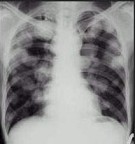

- 单项选择题男,45岁, HBV阳性十年,胸痛1月伴咳嗽, 咯血1天,胸片如图, 选择最可能的诊断是 ( )

A、HBV病毒肺部转移

B、肺多发性脓肿

C、金葡菌感染

D、肺转移癌

E、肺韦格氏肉芽肿